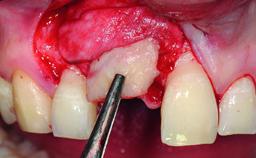

Bone Augmentation Horizontal|Simultaneous|Staged

Augmentation Materials Autogenous chips|Xenogenous|Membrane